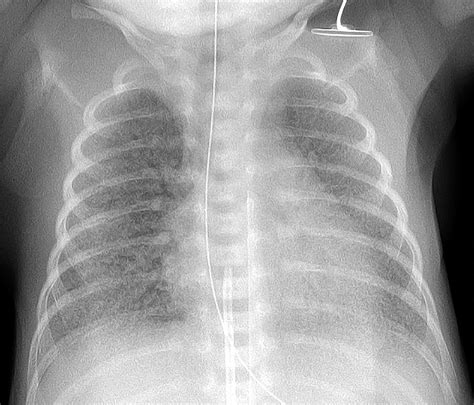

ARDS is a complex syndrome that can be triggered by various factors, including sepsis, pneumonia, trauma, and aspiration. It is marked by the rapid onset of bilateral pulmonary infiltrates, refractory hypoxemia, and decreased lung compliance. The Ards Chest X Ray is instrumental in visualizing these pulmonary infiltrates, which appear as diffuse, bilateral opacities on the radiograph.

The Ards Chest X Ray is often the first imaging modality used to evaluate patients suspected of having ARDS. It provides a quick and relatively inexpensive way to assess the lungs for signs of inflammation and edema. Key findings on an Ards Chest X Ray include:

• Bilateral pulmonary infiltrates

• Diffuse opacities

• Air bronchograms (air-filled bronchi surrounded by consolidated lung tissue)

• Absence of pleural effusions or cardiomegaly

These findings, when combined with clinical criteria such as the PaO2/FiO2 ratio (the ratio of arterial oxygen partial pressure to fractional inspired oxygen), help confirm the diagnosis of ARDS.

• Bilateral Infiltrates: ARDS typically presents with bilateral, diffuse infiltrates that are often more pronounced in the dependent lung zones.

• Air Bronchograms: These are visible air-filled bronchi within consolidated lung tissue and are a hallmark of ARDS.

• Absence of Pleural Effusions: Unlike other causes of pulmonary edema, ARDS is usually not associated with significant pleural effusions.

• Cardiomegaly: The heart size is typically normal in ARDS, helping to differentiate it from cardiogenic pulmonary edema.